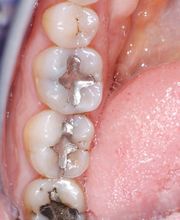

Das Bodensee Implantat Zentrum (ZIP) ist Ihre führende Praxis für Zahnheilkunde in der Region. Wir sind spezialisiert auf hochwertige Implantologie, einschliesslich des All-on-4® Konzepts, für das wir als Excellence Center Gold-zertifiziert sind. Unser Leistungsspektrum umfasst Komplettsanierungen, Kronen, Brücken sowie ästhetische Behandlungen. Mit über 30 Jahren Erfahrung bieten wir auch Angstpatienten eine einfühlsame Betreuung und Behandlungen unter Narkose für ein strahlendes Lächeln.